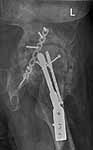

49 year old male, active speedskater, one year after MVC with multiple trauma and mild traumatic brain injury. Pipkin type IV fracture of the left hip. Same day ORIF through KL approach. No heterotopic ossification "prophylaxis". Day 7 wound revision for hematoma. Full weightbearing after 3 months. Full recovery except left hip function due to early severe HO. Function after one year: fixed ankylosis in 40 degrees flexion, 10 degrees exorotation. Patient frequently asks for attempt to improve hip function.

Preop - Click to Magnify